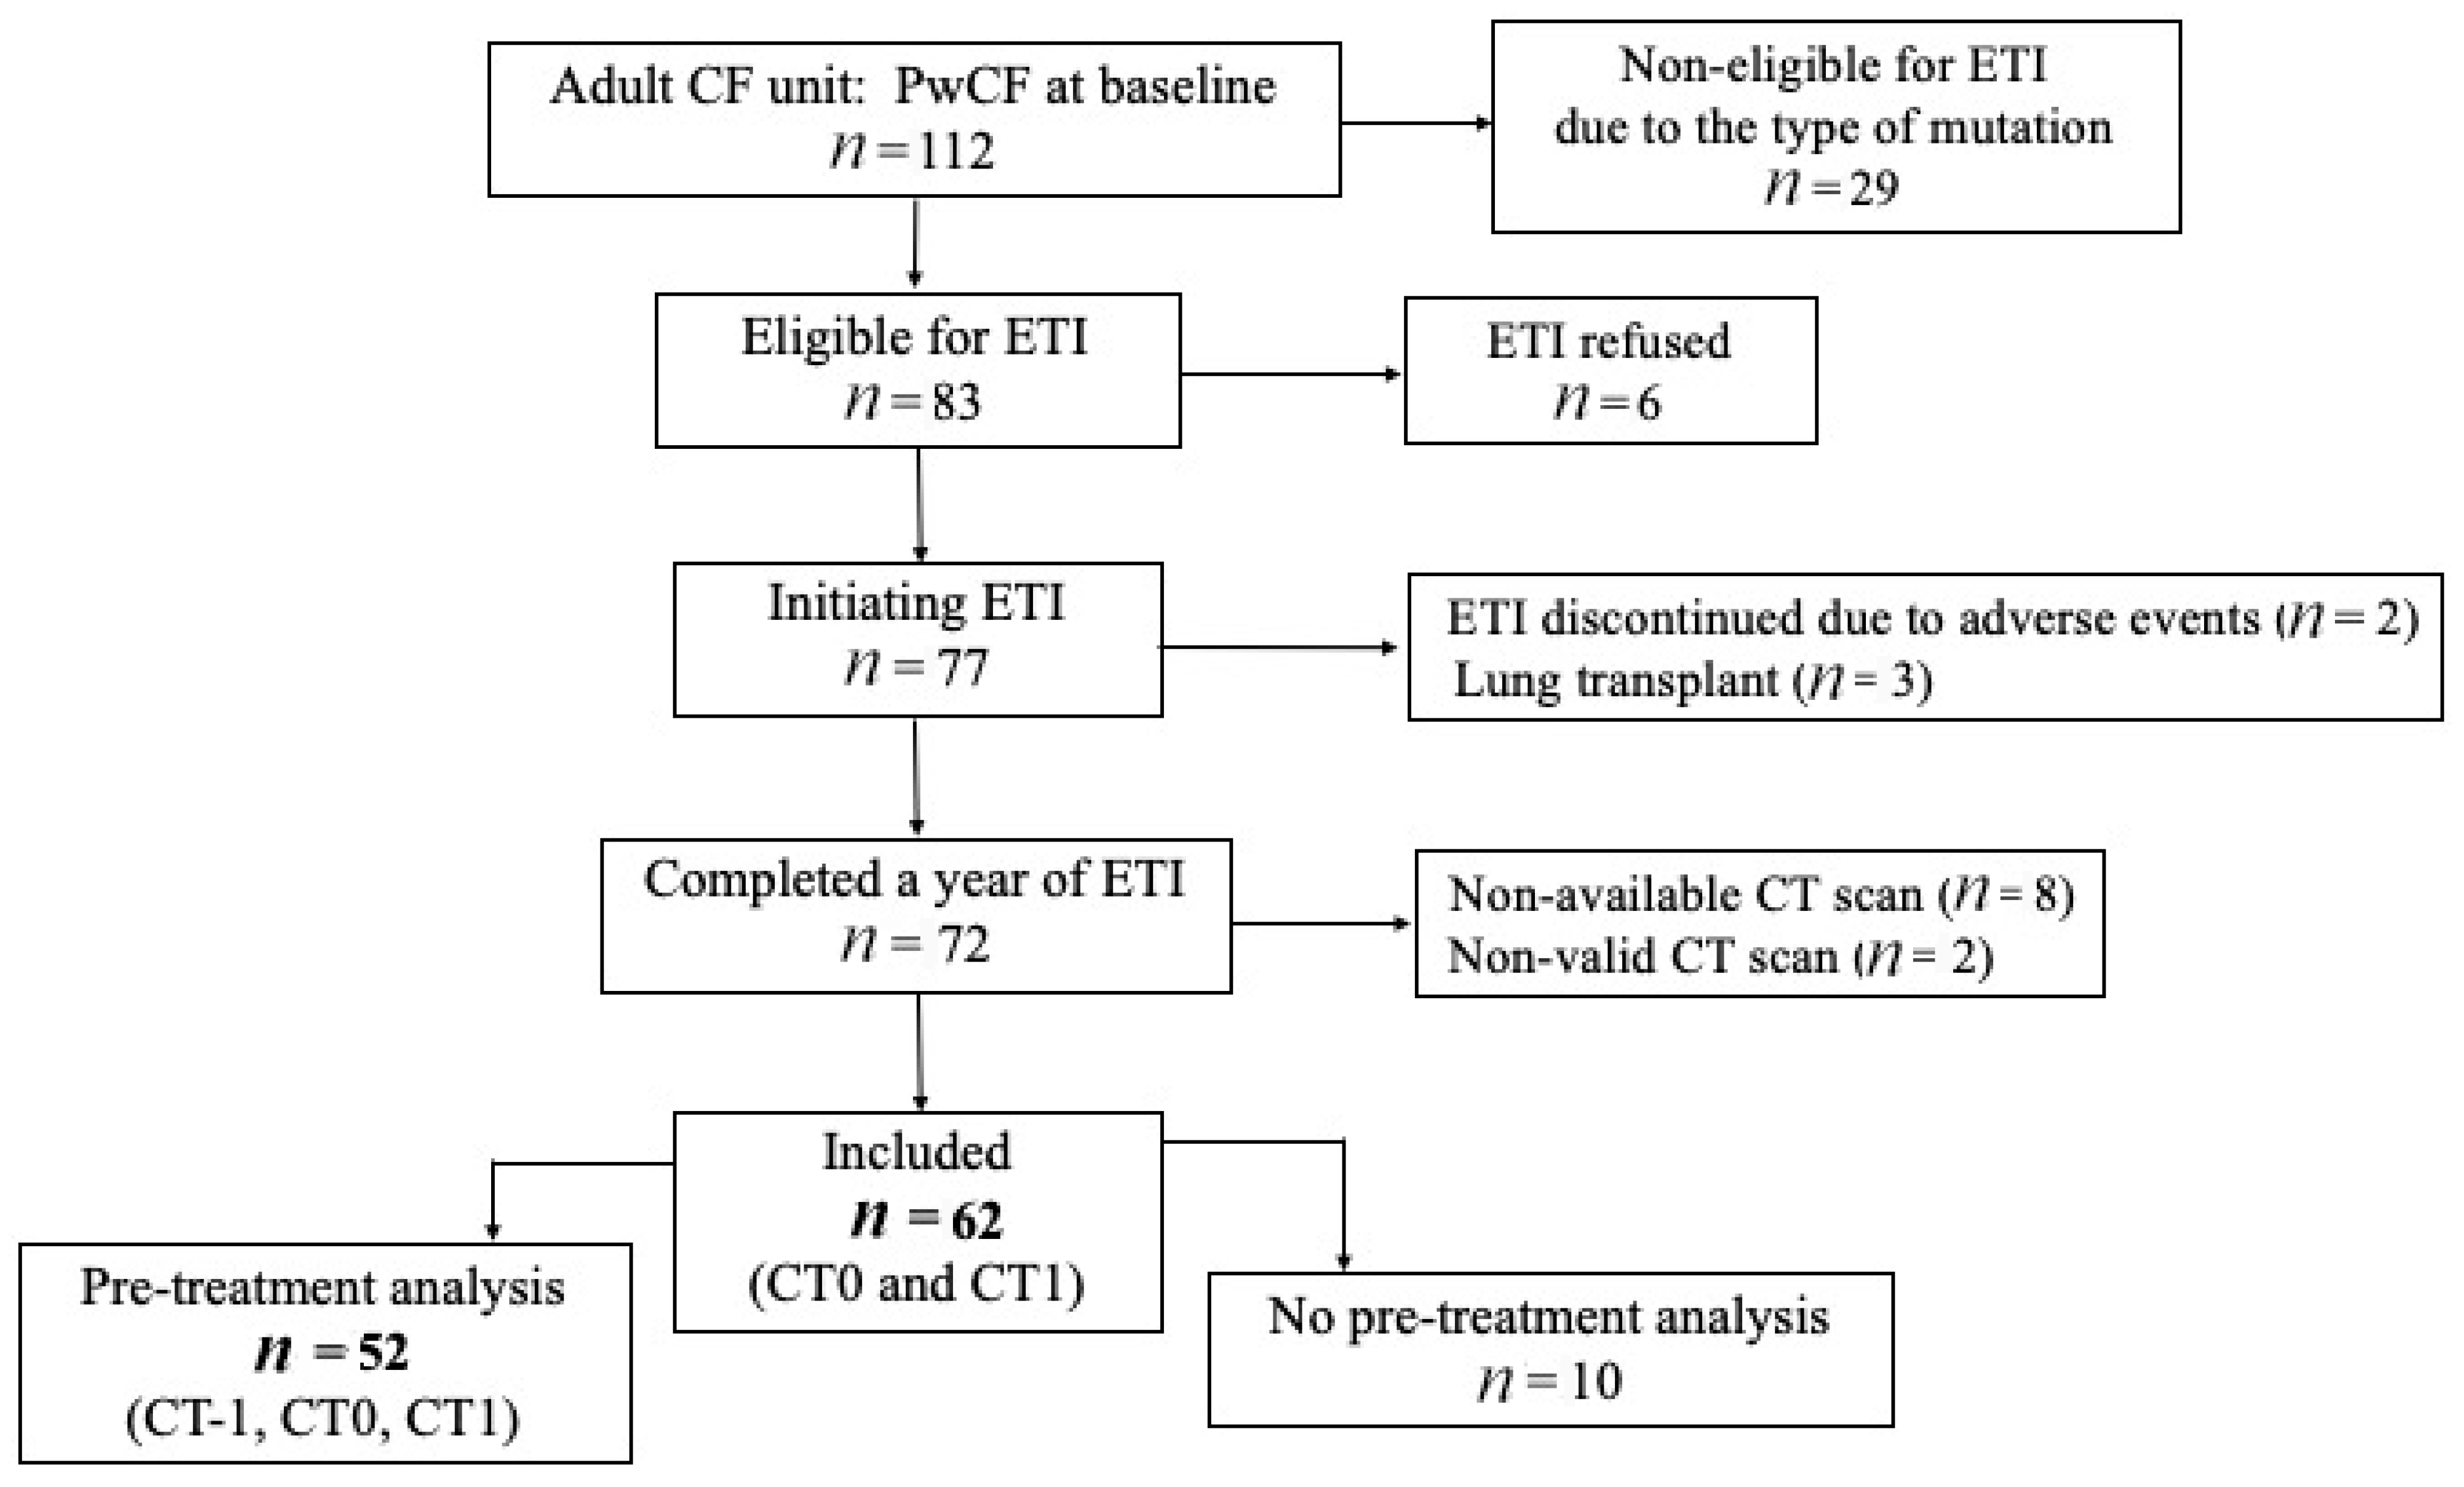

Of the 112 patients managed at the CF center between December 2021 and November 2022, 83 were deemed eligible for ETI by the pulmonologist. After excluding 21, a total of 62 adults with CF (35 males) met the inclusion criteria (Figure 1). The median age at the initiation of ETI was 30.4 (±7.87) years, and 54.8% harbored a heterozygous mutation. The demographic and clinical characteristics of the study cohort are summarized in Table 1.

Figure 1.

Study flow chart. CF: cystic fibrosis. ETI: elexacaftor–tezacaftor–ivacaftor. PwCF: people with cystic fibrosis.